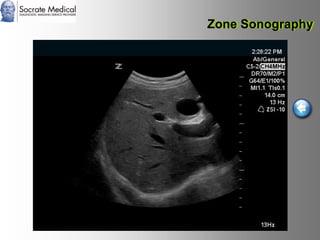

Il documento presenta la tecnologia della zone sonography, che promette una rivoluzione nel campo degli ultrasuoni, superando i limiti dei sistemi tradizionali grazie a metodi di acquisizione dati più veloci e una gestione delle informazioni migliorata. Questa tecnologia consente una maggiore definizione dell'immagine, una riduzione degli artefatti e un'ottimizzazione del processo diagnostico, con vantaggi in termini di tempo e costi. Inoltre, il channel domain processing e la zone speed technology offrono applicazioni avanzate e miglioramenti nella sicurezza diagnostica.